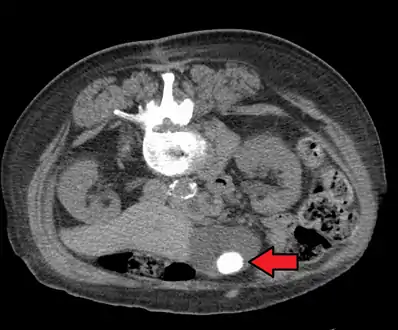

A 1.9 cm gallstone impacted in the neck of the gallbladder and leading to cholecystitis as seen on ultrasound. There is 4 mm gall bladder wall thickening.

On abdominal ultrasound, sinking gallstones usually have posterior acoustic shadowing. In floating gallstones, reverberation echoes (or comet-tail artifact) is seen instead in a clinical condition called adenomyomatosis. Another sign is wall-echo-shadow (WES) triad (or double-arc shadow) which is also characteristic of gallstones.[38]

Diagnosis is typically confirmed by abdominal ultrasound. Other imaging techniques used are ERCP and MRCP. Gallstone complications may be detected on blood tests.[2]